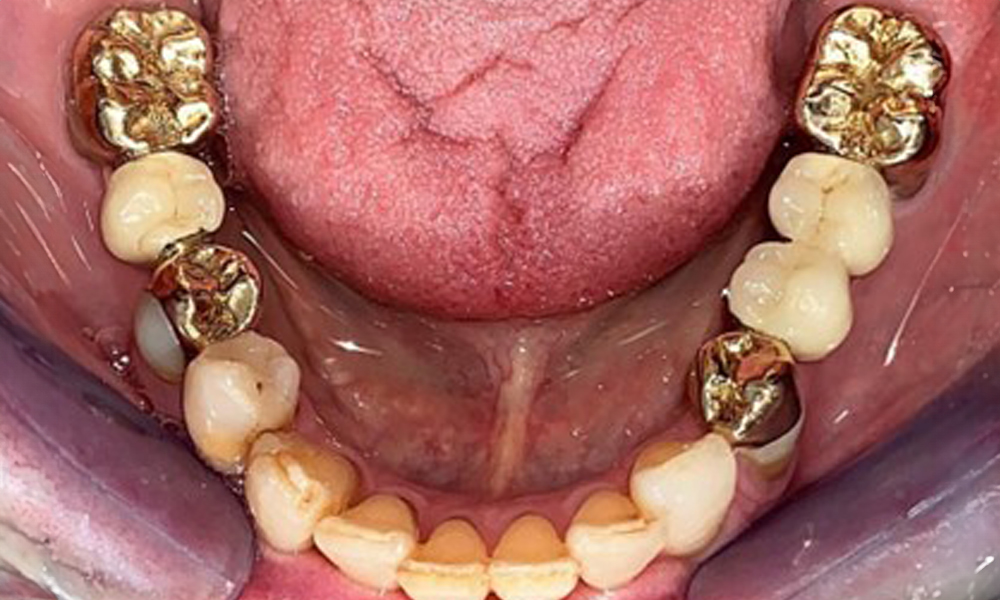

Occlusal view of the mandible.

Fig. 4: Occlusal view of the mandible.

The dental findings are as follows: Combined removable implant and tooth-supported telescopic prostheses on implants 15, 13, 21, 23, 24, 25 and tooth 11 (Fig. 1, Fig. 2, Fig. 3). The patient was fitted with a fixed mandibular denture. Adequate bridges were present over 37 to 34 and 45 to 47 (Fig. 4), the crown margins were intact and there were no active caries. A composite filling with a marginal gap was present on tooth 43. There was mandibular gingival recession, exposing 1 to 3 mm of root surface. This also applies to 11.

The radiological findings show partially edentulous dentition with maxillary implants for teeth 15, 13, 21, 23, 24, 25 and a telescopic crown on tooth 11. Adequate mandibular bridges spanning 37 to 34 and 45 to 47 are present. 48 is impacted. There are suspected secondary caries distally on 43 and mesially on 44. 44 is restored with a non-radiopaque cavity lining. There is generalised horizontal bone loss of approx. 10% to 30% and localised vertical bone loss affecting teeth 22 and 42 (Fig. 5).